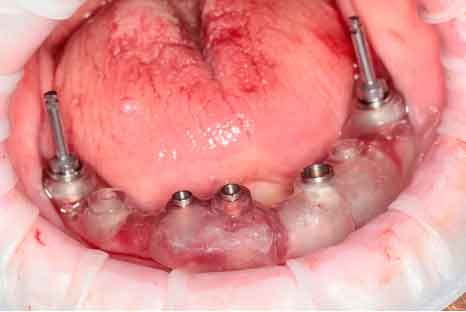

Photo - Situation intra-orale

Modèles 3D - Occlusion obtenue par la caméra intra-orale

Avant d'acquérir le CBCT, j'ai ajouté 2 morceaux de composite à la mandibule pour pouvoir effectuer le processus de picking pendant le protocole MODJAW. Il s'agit d'une astuce utile à retenir en cas d'absence de dents.